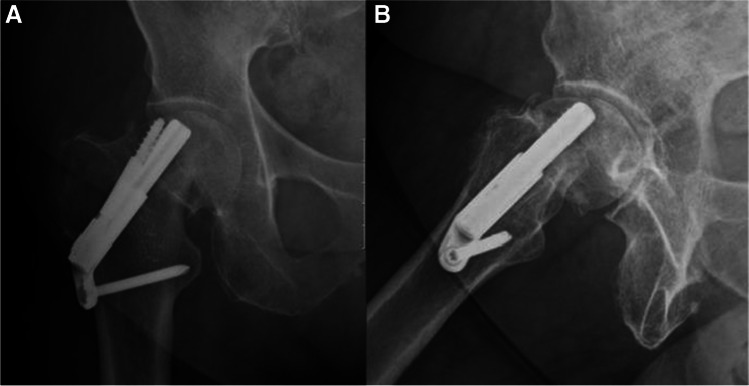

Fig. 2.

A, B AP and lateral radiographs postoperative day 1, demonstrating fixation of the fracture with FNS

Fig. 3.

A, B AP and lateral radiographs 6 weeks after the surgical treatment. Radiographs demonstrate failure of fixation, cut-out of the implant. After the initial surgery, the patient was discharged home with instruction to full weight bear on the operated leg and was referred for physiotherapy treatment. Patient suffered from progressive hip pain and limp, walked short distance with the aid of a Zimmer frame. She was treated with revision surgery, hemiarthroplasty of the right hip